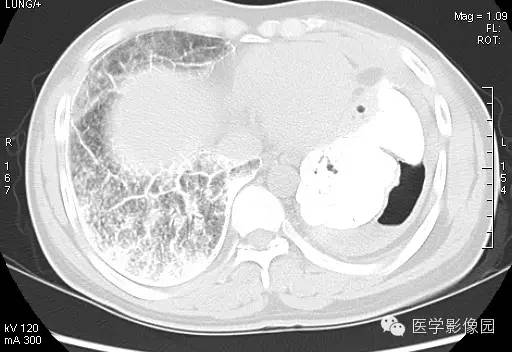

【病例】尘肺1例X线及CT影像表现

男性,36岁,镀锌工作史1年。

尘肺的主要病理改变为肺间质弥漫性纤维化及弥漫性灶周肺气肿,主要累及周围肺组织和支架结构,如肺泡壁、小叶间隔和支气管血管周围组织。

小结节影:多为双肺弥漫性或散在小结节影,表现为类圆形影,边界清晰,以中下肺为主,背侧多见。

大阴影:多为块状大阴影,表现为不规则卵圆形影,边缘凹凸不平,多有粗大索条影,伴疤痕性肺气肿,其内可见点状、斑片状钙化,坏死或空洞。

胸膜改变:可见胸膜肥厚、粘连及钙化缘怨例。

肺门改变: 肺门影增大,肺门多伴点状或蛋壳状钙化。

肺纹理:扭曲及变形改变。